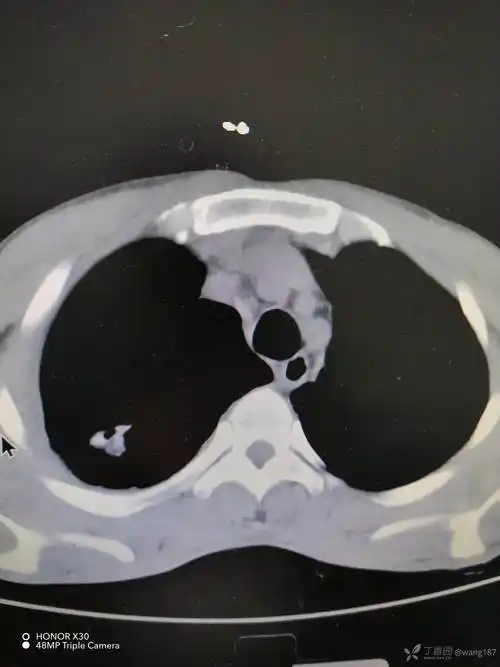

青年男性的胸腔积液